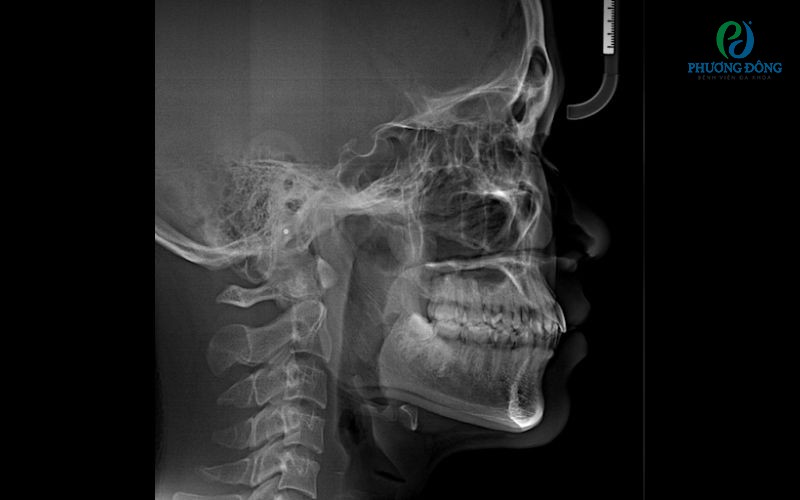

Chẩn đoán cận lâm sàng

Để xác định chính xác tình trạng, bác sĩ sẽ chỉ định các kỹ thuật hỗ trợ gồm:

• So sánh mẫu hàm bằng thạch cao.

• Chụp X-quang toàn cảnh (Panorama).

• Chụp phim sọ nghiêng (Cephalometrics).

Những hình ảnh này giúp đánh giá sự tương quan giữa hai cung hàm và mức độ lệch của răng.

Chụp X-quang giúp đánh giá được mức độ lệch của răngChụp X-quang giúp đánh giá được mức độ lệch của răng